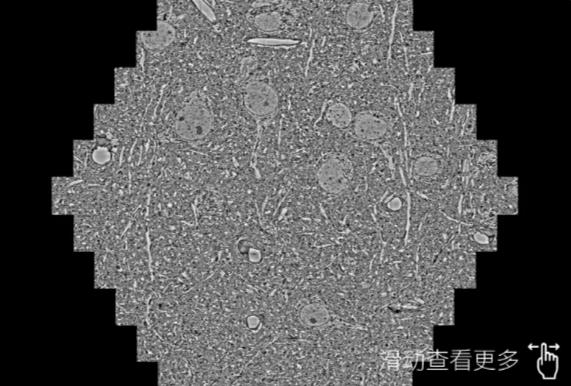

鼠脑切片。左图使用通州蔡司通州扫描电镜MultiSEM706对165μmx143pm面积区域成像,耗时仅需1.5秒。右图为鼠脑切片中30μm区域放大效果。样品由芝加哥大学B.Kasthuri提供。

使用蔡司高速通州扫描电镜MultiSEM对1mm²人脑皮层组织进行高分辨成像,并对其中的各种细胞结构进行三维重构分析。左图展示了2x3mm²组织平面中锥体神经元的三维重构效果。右图显示了局部体积神经元三维重构。图像由哈佛大学chtman实验室提供,渲染图由D. Berger 制作。